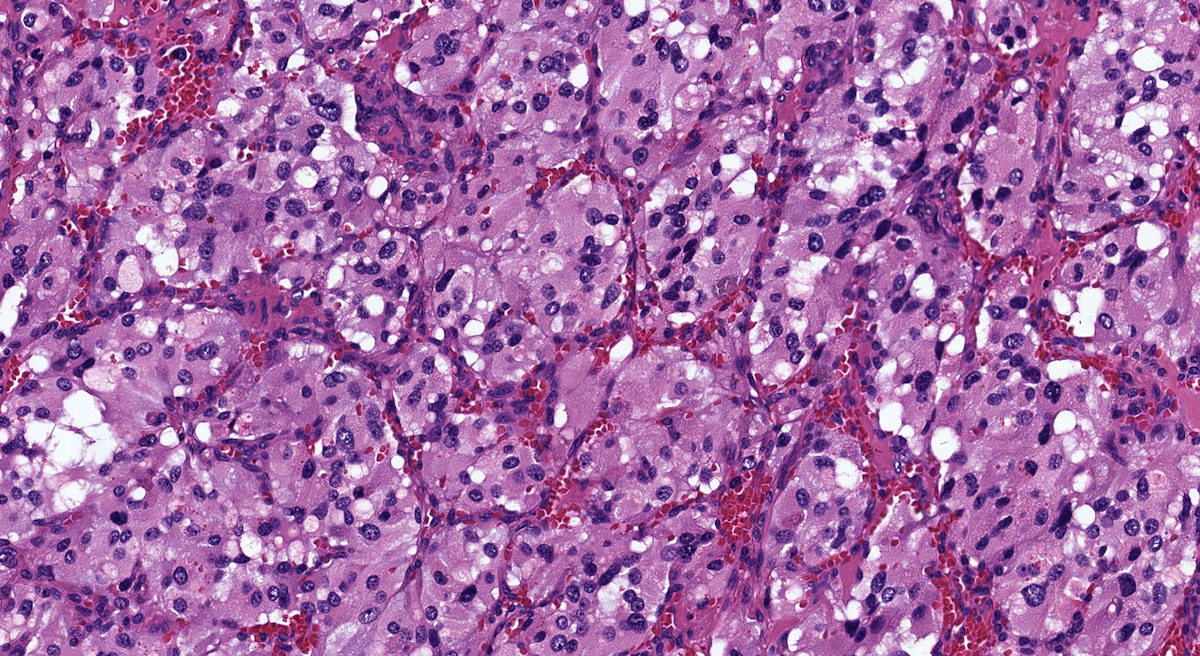

Microscopic (histologic) description

- Prevailing histologic pattern: epithelioid chief cells arranged in distinctive clusters / nests (zellballen pattern), separated by prominent fibrovascular stroma (J Clin Med 2018;7:280)

- Chief cells: round, oval to polygonal cells with abundant granular basophilic, eosinophilic or amphophilic cytoplasm (Surg Pathol Clin 2019;12:951)

- Intracytoplasmic hyaline globules may be present in sympathoadrenal paragangliomas

- Giant multinucleated cells and bizarre cells can be present (Srp Arh Celok Lek 2002;130:7)

- Rarely, elongated and spindle shaped cells with a sarcomatoid appearance may be found

- Scattered ganglion cells can be seen

- May have nuclear atypia

- May have dysmorphic vessels, melanin-like pigment (neuromelanin) (pigmented paraganglioma), amyloid, abundant stroma and osseous metaplasia (Diagn Pathol 2012;7:77, Hum Pathol 1992;23:33)

- No or rare mitotic figures except in highly aggressive rapidly proliferating lesions

- May have focal chronic inflammatory infiltrate

- Necrosis is unusual except in patients who have undergone preoperative tumor embolization

Microscopic (histologic) images

Contributed by Luvy Delfin, M.D. and Sylvia L. Asa, M.D., Ph.D.